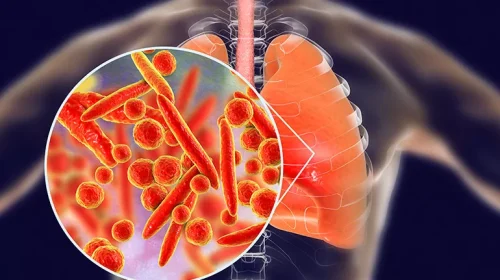

Tuberculosis (TB)

Tuberculosis (TB) is a serious illness that mainly affects the lungs. The germs that cause tuberculosis are a type of bacteria. Tuberculosis can spread when a person with the illness coughs, sneezes or sings